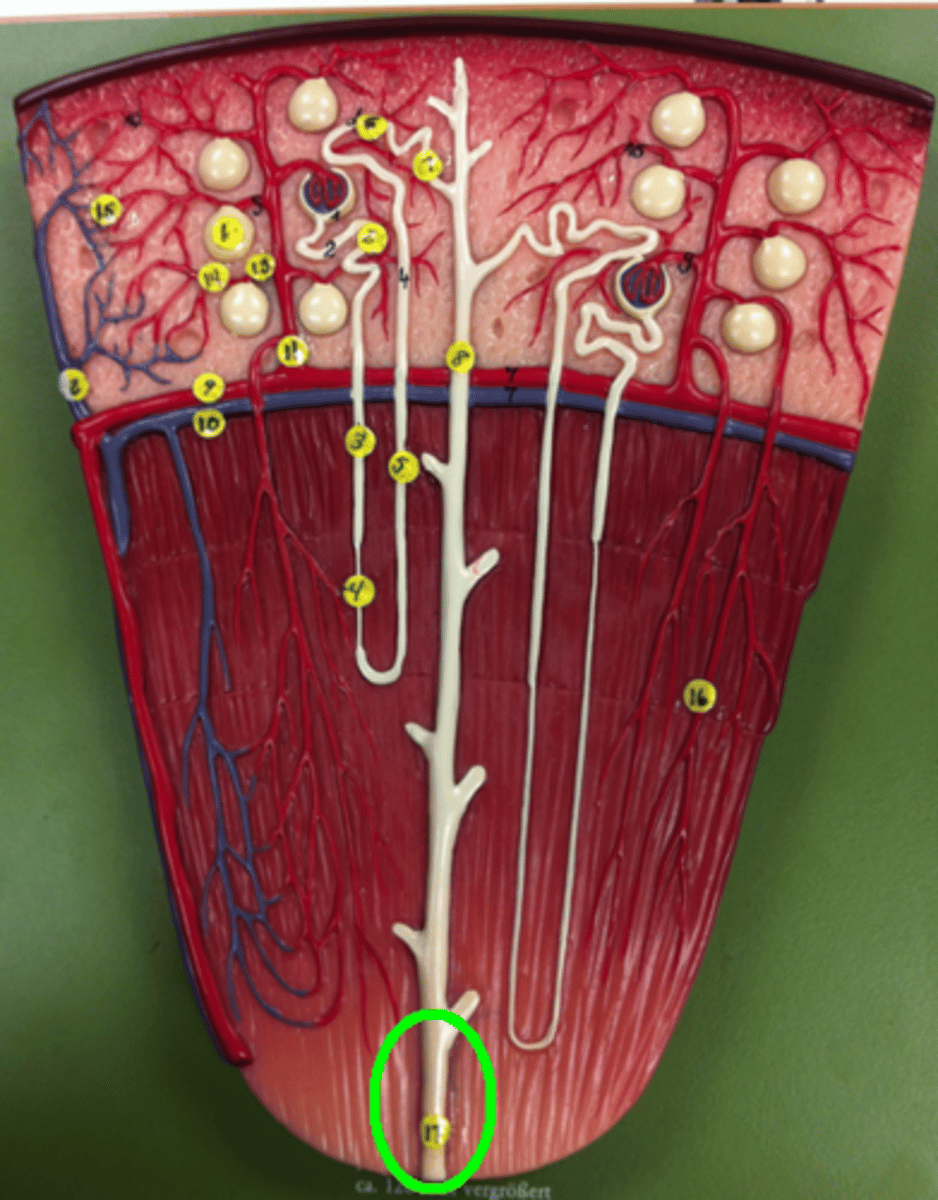

interlobar

both vessels

interlobular

both vessels

arcuate

both vessels

afferent arteriole

efferent arteriole

proximal convoluted tubule

descending loop of henle

ascending loop of henle

distal convoluted tubule

papillary duct

collecting duct